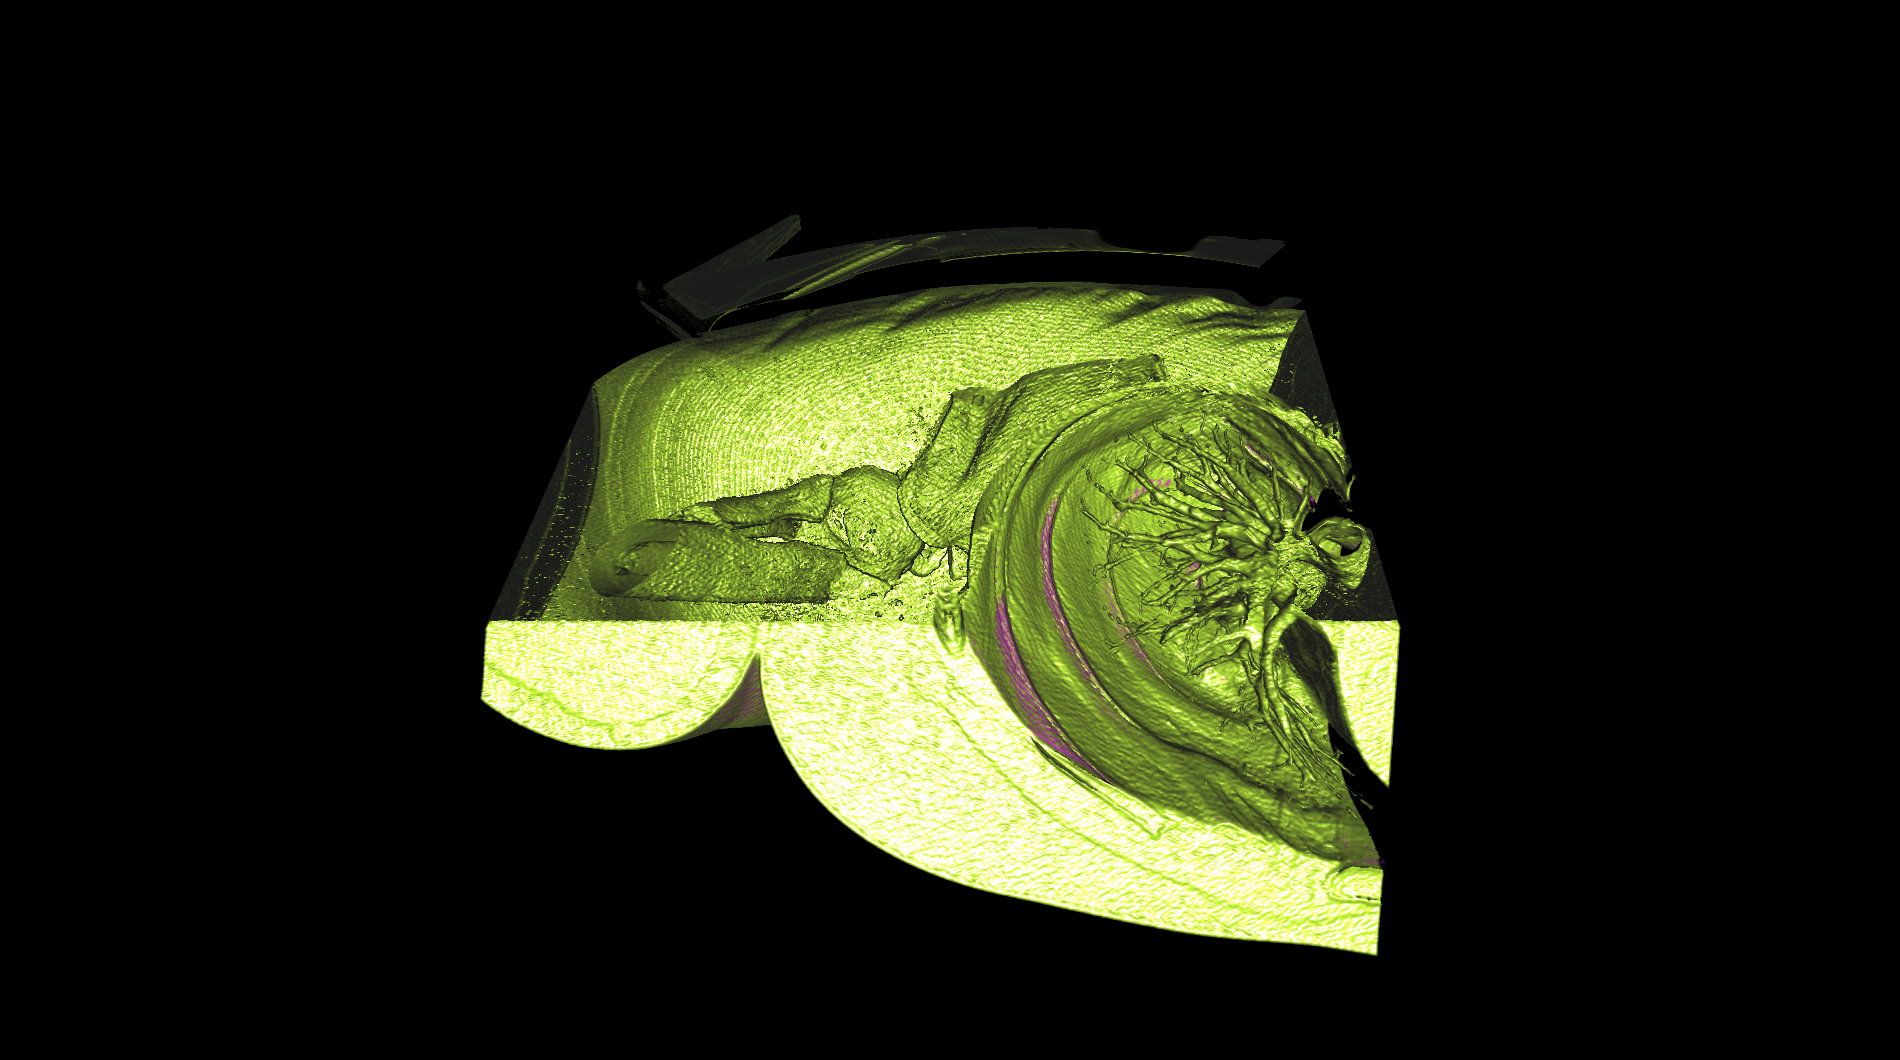

| The medical-04 workload evaluates medical visualization techniques using the Tuvok library and OpenGL API. It features slice rendering and raycasting with 1D and 2D transfer functions, exploring datasets from a beating heart, brain, and alligator. Clipping planes and varying voxel densities test performance in medical imaging workflows, simulating scenarios like MRI and CT analysis. | |||

| Composite Score: | 271.71 | ||

| Graphics Renderer: | RTX 6000 Ada Generation | ||

| Index | Description | Weight | Result (FPS) |

| 9 |

Raycasting of an alligator with 2D transfer

Raycasting of an alligator with 2D transfer

|

10.00 |

26.71

|

| 10 |

Raycasting of an alligator with 2D transfer and clipping plane

Raycasting of an alligator with 2D transfer and clipping plane

|

10.00 |

49.60